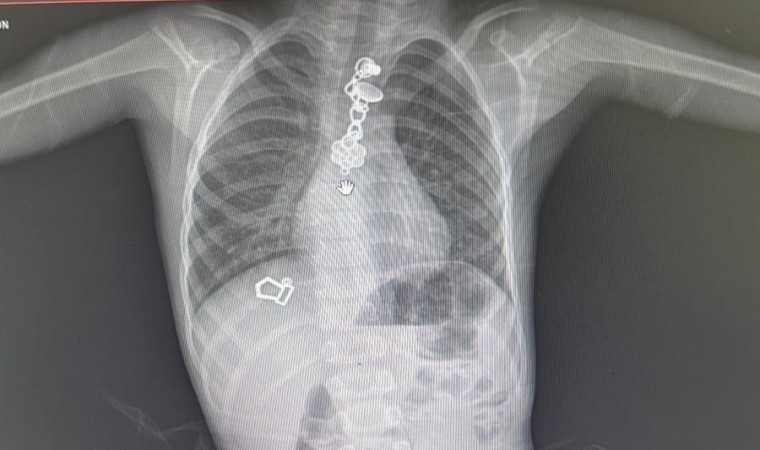

Boğazlarına yabancı cisim kaçan ve idil ile Şırnak Devlet Hastanelerinden Cizre Devlet Hastanesine sevk edilen 3 çocuk Göğüs Cerrahi Uzmanı Op. Dr. Serdar Munis’in bronkoskopi ve özufagoskopi cihazı ve ameliyat ortamında yaptığı başarılı tıbbi müdahale ile sağlıklarına kavuştu. 2,5 yaşındaki Ali Asaf Kutlu, 3 yaşındaki Maşallah Aydın ve 5 yaşındaki Miraç Akhan Op. Dr. Serdar Munis’in bronkoskopi ve özufagoskopi cihazı ile ameliyat ortamında yaptığı başarılı tıbbi müdahale ile sağlığına kavuştu.

Rijit bronkoskopi ve özufagoskopi cihazlarının Şırnak’ta bulunmasının hastalar açısından hayati bir öneme sahip olduğuna vurgu yapan Cizre Dr. Selahattin Cizrelioğlu Devlet Hastanesi Göğüs Cerrahi Uzmanı Op. Dr. Serdar Munis, "Şırnak ili genelinde rijit bronkoskopi ve özufagoskopi cihazları olmadığından dolayı hastayı hayatı riske sokan böylesi durumlarda, hastalar ambulanslar ile bu müdahalenin yapıldığı en yakın merkez olan Diyarbakır’daki sağlık kuruluşlarına sevkleri yapılmaktaydı. Bu cihazların temininden sonra çok kısa bir zaman diliminde 3 hastaya müdahale edilmiş olup 3 hastanın nefes ve yemek borularına kaçan yabancı cisimler çıkartılmıştır. Hastalara yerinde ve erken müdahale edilmeleri, hem hastaların sağlığı açısından, hem de sağlık çalışanlarının iş yükünü hafifletmek açısından yerinde bir sağlık müdahalesi imkanı olmuş ve hastalarımız yapılan tıbbi müdahale ile sağlıklı bir şekilde taburcu edilebilmişlerdir" dedi.